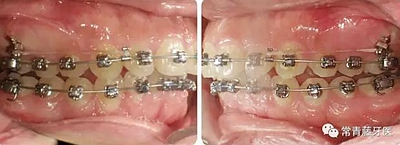

治療8個月,換0.018*0.025"CuNiTi弓絲,植入支抗釘,植入位點(diǎn)為上頜第一磨牙根上方顴牙槽嵴處,使其與牙根平行。同時嘗試性牽引遠(yuǎn)移上牙列。

治療12個月,更換為0.018*0.025”不銹鋼方絲,鎳鈦螺旋彈簧牽引內(nèi)收上牙列,同時下頜配合Ⅱ類牽引。